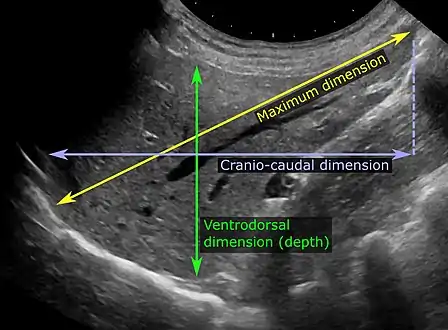

Ultrasonography of liver tumors involves two stages: detection and characterization. Tumor detection is based on the performance of the method and should include morphometric information (three axes dimensions, volume) and topographic information (number, location specifying liver segment and lobe/lobes). The specification of these data is important for staging liver tumors and prognosis. Tumor characterization is a complex process based on a sum of criteria leading towards tumor nature definition. Often, other diagnostic procedures, especially interventional ones, are no longer necessary. Tumor characterization using the ultrasound method will be based on the following elements: consistency (solid, liquid, mixed), echogenicity, structure appearance (homogeneous or heterogeneous), delineation from adjacent liver parenchyma (capsular, imprecise), elasticity, posterior acoustic enhancement effect, the relation with neighboring organs or structures (displacement, invasion), vasculature (presence and characteristics on Doppler ultrasonography and contrast-enhanced ultrasound (CEUS).